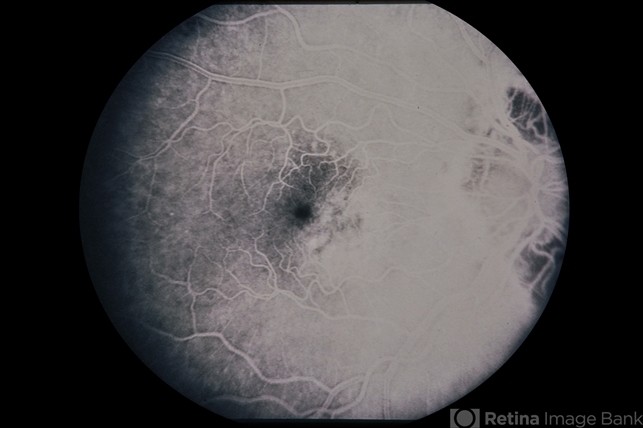

Nevus With CNVM

nevus

Nevus with CNVM in an 81-year-old patient.